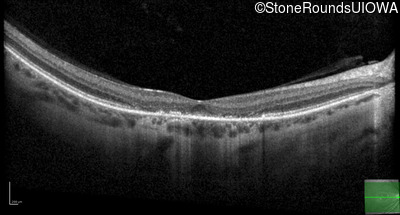

Optical Coherence Tomography - Right - 5/700

Exemplar / OCT Stack